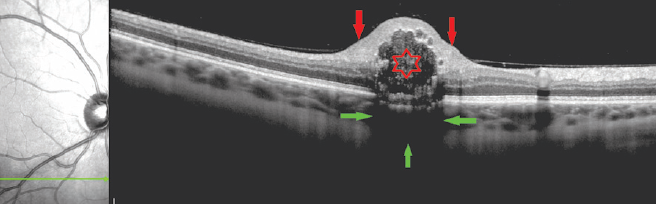

OCT investigations revealed a local elevation of the retinal profile. A thickening of the retinal inner layers was primarily identified at the edges of the lesion and at the nerve fibers layer. On the other hand, large cavities with uneven sharp contours and an intensely hyperreflective wall were noticed in the center of the focus, represented by mulberry-shaped patterns. Multiple hyperreflective inclusions were also found inside the cavities. The choroid thickness in the focal zone did not differ from the adjacent zone, however, it was impossible to evaluate its structure as a result of partial screening and the manifestation of artifacts (Fig. 15), similar to the reverberation effect in US.

Fig. 15. Optical coherence tomography - horizontal scan across the maximal prominence of retinal astrocytoma. Asterix – a cavity in the center of the focus; red arrows – thickening of the inner layers of the retina along the edges of the focus; green arrows – zone of partial shielding of underlying structures

Рис. 15. Оптическая когерентная томография — горизонтальный срез через зону максимальной проминенции астроцитомы сетчатки. Звёздочка — полость в центральной части очага; красные стрелки — утолщение внутренних слоёв сетчатки по краям очага; зелёные стрелки — зона частичного экранирования подлежащих структур

Finally, and as opposed to the diseases described above, the pathological process of RA tends to localize in the retinal inner layers. Despite the fact that the choroid remains intact, its visualization is significantly complicated because of pronounced retinal changes (involving a thickening of the retinal inner layers, the presence of large cavities with uneven clear contours and intensely hyperreflective wall, and multiple hyperreflective inclusions), that can, in turn, block the signal stemming from the underlying tissues.